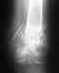

28лет175см76кг10 лет назад перелом бедра, остеосинтез, год назад начались странные проблемы с ногой.постоянно возростающий скрип, хруст и щелчки под коленной чашечкой (ДЗ: посттравматичесский пателло-феморальный артроз)2.также непонятно с тазобедренным суставом, он издает немонятные стуки при хотьбе (люфт?) прямо или по лестнице (если приложить к бедру руку.)если стопа и вся нога повернута внутрь, то стука и люфта нетунога немного ноет во сне.3. почему кости левой ноги на КТ выглядят темнее? это остеопороз изза пластины??КТhttps://drive.google.com/file/d/0Bz7E_s0aLLmPVjEtWWw1OV9vSm8/edit?usp=sharingспасибо.